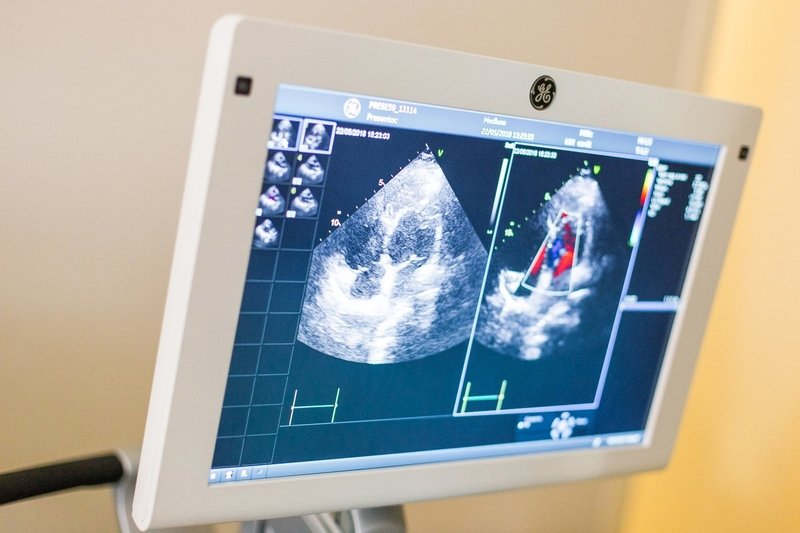

Но длительные наблюдения нужны далеко не всем. Чаще всего пациенту хватает одного посещения клиники, чтобы здесь же, в кабинете функциональной диагностики, пройти ЭКГ, эхокардиографию на аппаратах экспертного класса, а при необходимости — велоэргометрию, электроэнцефалографию, электромиографию, УЗИ щитовидной железы, почек, исследования крови на липиды, если понадобится — ангиографию в отделении лучевой диагностики, попутно получить консультации всех необходимых специалистов — невролога, ревматолога, оториноларинголога.

«Это наш важнейший принцип — не прогнать пациента по стандартной схеме исследований, а докопаться до причины, решить даже самую сложную диагностическую задачу, чтобы потом сконцентрироваться на эффективном лечении. Наши возможности, включая УЗИ сердца плода, позволяют диагностировать болезни сердечно-сосудистой системы в любом возрасте», — говорит доктор Иванова, уже готовая к приёму следующего пациента.